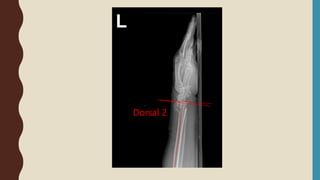

Dorsal 2

RADIOGRAPHIC FINDINGD

• Extra or intra-articular fracture

• Dorsal angulation

• Dorsal tilt

• Dorsal comminution

• Radial shortening

• Ulnar styloid fracture

• ( Ulnar variance )